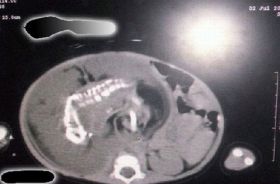

Medicii din Arabia Saudita au facut publice si radiografiile care demonstreaza ca, intr-adevar, in abdomenul fetitei evolueaza o sarcina. In prezent, doctorii incearca sa gaseasca cea mai buna metoda de a-i salva viata copilului.